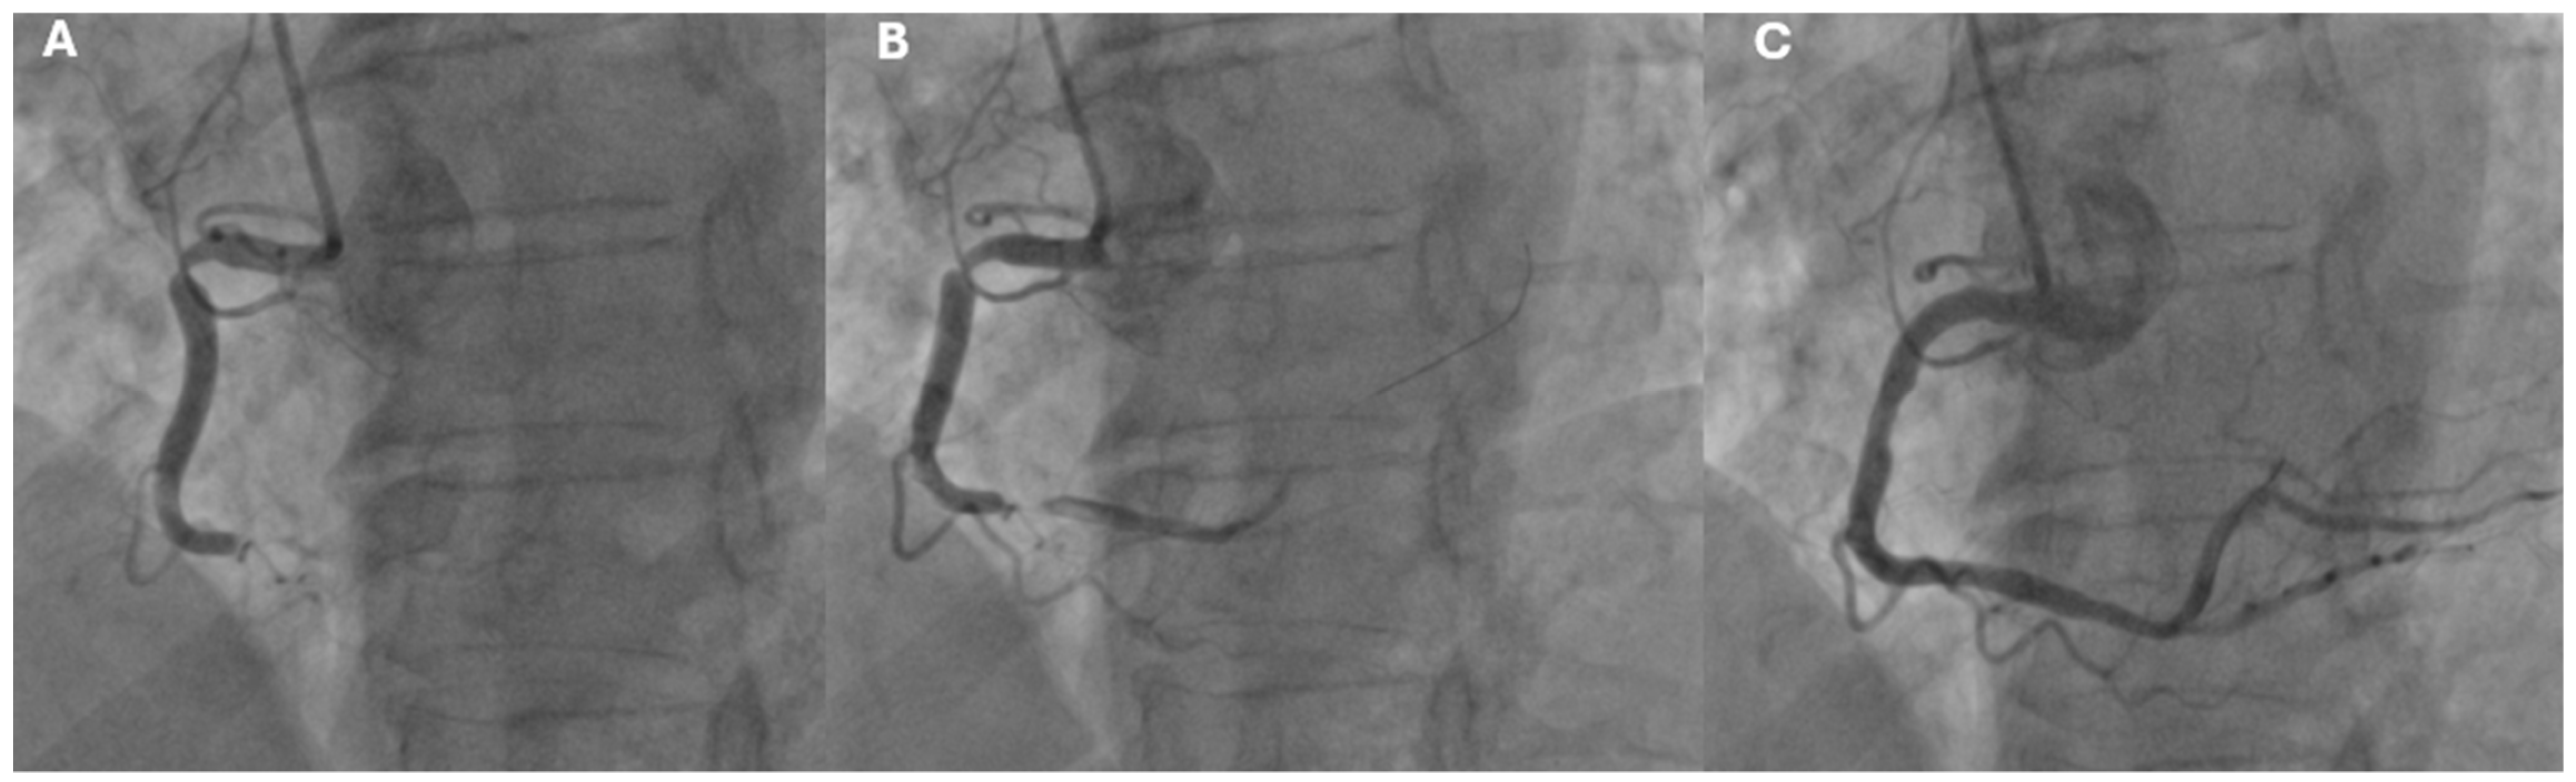

- STEMI (ST-Segment Elevation Myocardial Infarction): Defined by persistent ST-segment elevation on the ECG, typically indicating complete blockage of a coronary artery (Figure 2).

3.1. Diagnostic Approach in Acute Coronary Syndrome

4.1. Treatment of Acute Coronary Syndrome